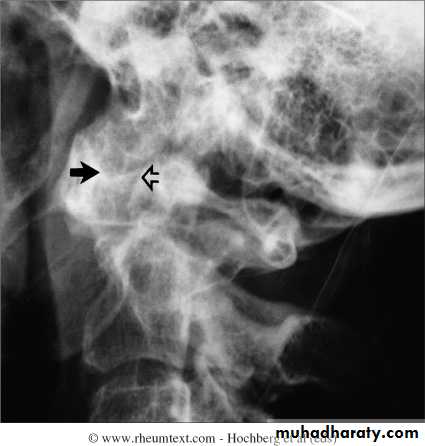

Severe destruction of the distal radius and ulna.Atlanto-axial subluxation in RA

Always a concern in patient with longstanding RA and neck pain or cervical neurological symptomsBoutonniere deformity